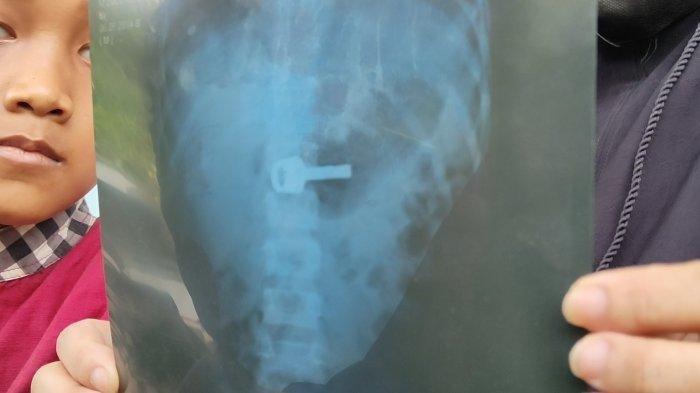

Nina saat menunjukkan rontgen kunci gembok yang bersarang di lambung anaknya di Jalan Talang Tembaga Keluarahan Lemahabang, Kecamatan/Kabupaten Indramayu, Selasa (20/9/2022).

Hasil rontgen menunjukkan bahwa kunci itu saat ini berada di bagian lambung bocah tersebut.

Ia harus menjalani operasi untuk mengangkat kunci tersebut dari dalam tubuhnya.

Tim medis mengkhawatirkan, kunci yang ada di tubuh bocah itu bisa saja turun sampai ke usus.

"Karena kalau sudah di usus bisa mengakibatkan infeksi pada ususnya," ujar dia.